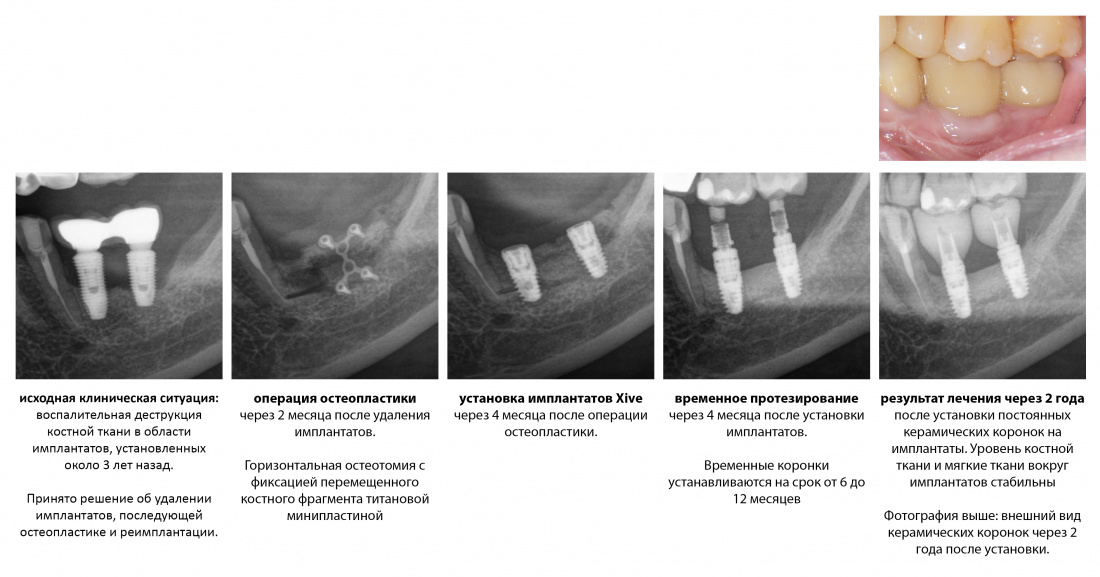

К последним, несомненно, стоит отнести операции имплантации с одновременной костной аугментацией. Те самые случаи, когда мы при установке имплантата наращиваем костную ткань вокруг него.

В отличие от принятого ранее последовательного подхода, проведение остеопластики одновременно с имплантацией позволяет сократить как время, так и травматичность имплантологического лечения, а также в какой-то мере снизить его стоимость.

Это позволило сократить сроки лечения в большинстве случаев до 3-4 месяцев, упростить и удешевить саму стоматологическую реабилитацию.